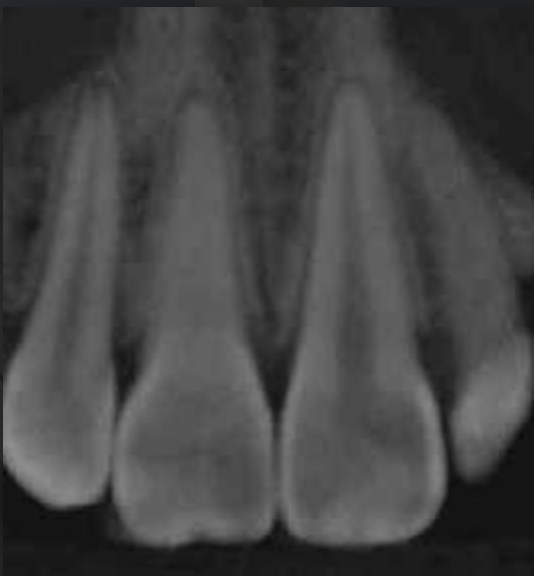

CALCIFICADOS